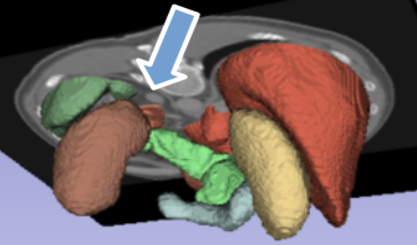

Figure 1: Shall we label the gray spot indicated by the blue arrow adrenal gland? (a) scan slice, (b) ground truth (with adrenal gland label removed) 3D segmentation around the slice, (c) all baseline segmentation wrongly segmented the spot as gland, and (d) AIC-Net gives correct segmentation.

So, what causes existing segmentation models to find it difficult to recognize anatomical features, which humans can grasp from just a handful of examples, despite being trained on hundreds of thousands of instances? AI-driven segmentation models are trained to detect organs solely from CT/MRI scans (Çiçek et al. 2016; Chen et al. 2018; Hatamizadeh et al. 2021). Ideally, a robust model should extract both local and global features, using global features to distinguish similar-looking local features. However, we often observe that when relying solely on the scan as input, these models tend to overlook learning global patterns. For example, in the scan slice shown in Figure 1(a), base on local patterns it is difficult to tell if the gray spot, as indicated by the blue arrow, should be segmented as left adrenal gland or not. It is positioned directly above the right kidney, where the gland typically appears, and has similar intensities to the average adrenal gland. All baseline models we tested wrongly segmented it as part of the left adrenal gland, as shown in Figure 1(c). However, this results in a separated component of the gland, clearly violating the anatomy. Our proposed method can give correct segmentation.